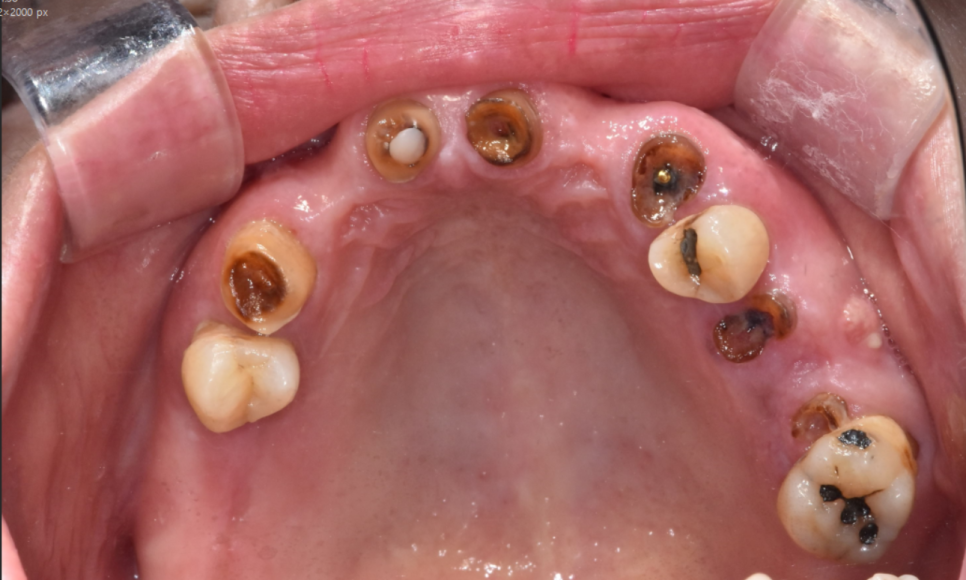

다수의 치아 상실

23.08.17

그동안 식사를 어떻게 하셨는지

잘 모르겠을 정도로

치아가 많이 상실된 상태였습니다.